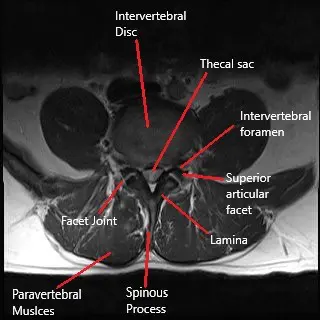

An imaging study in the form of an MRI is used to diagnose re-herniation. MRI studies with gadolinium may be used to differentiate between scar tissue and re-herniation. Other imaging studies such as an X-ray and a CT scan are more commonly used to visualize the bony anatomy of the patient. The evaluation of the bony anatomy helps in the planning of a subsequent surgery if needed.